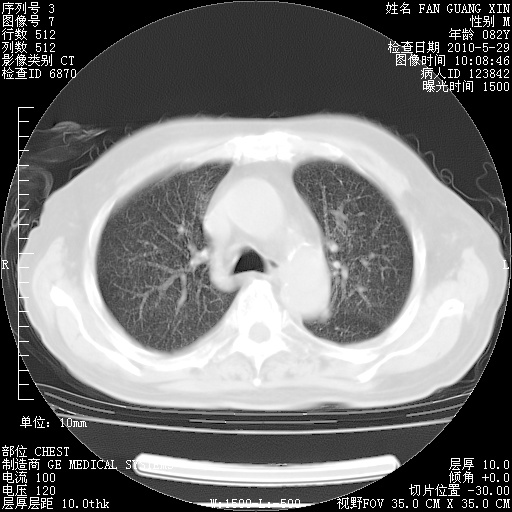

再治疗10天后的肺部CT

从白细胞总数和中性比例看好像合并感染。肺部纹理好像比上次多,支气管炎?其他感染?

阅读此次胸部CT,肺间质渗出性改变较入院时有吸收。目前从体温、白细胞、中性分叶明显增高,肯定存在细菌感染(发生医院感染哦,若无消化道及泌尿系统等感染的依据,肺部感染可能大)。若你院头孢哌酮舒巴坦钠耐药率较高,同意你的方案,若48小时体温仍高,可考虑使用碳青霉稀类抗菌药物,同时可予超声雾化、注意滴数时加大液体量。白蛋白33.30g/L较低哦,需加强营养等支持治疗。